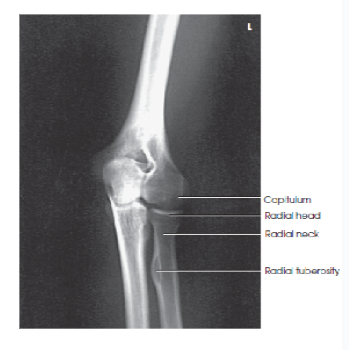

Structures shown/evaluation criteria for AP elbow

• think ulna

-joint space

-epicondyles

-fossae

A

radial head, neck, and tuberosity slightly superimposed over the proximal ulna

elbow joint open and centered to CR

no rotation of humeral epicondyles

coronoid and olecranon fossae approximately equidistant to epicondyles

eval/structures: how should the elbow joint appear in an AP oblique elbow lateral rotation position?

open and centered to the central ray

Q

Eval/structures: how can you tell the elbow is in a 45 degree lateral rotation?

the radial head, neck, and tuberosity are projected free of the ulna

elongated lateral humeral epicondyle